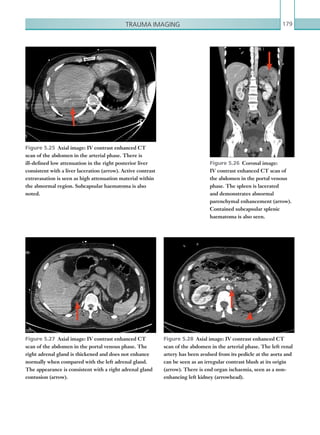

colorectal malignancy without bowel obstruction, the

quantityoffreeairisusuallysmallandloculesofairtend

to be concentrated in close proximity to the involved

colonic loops. The presence of free air, phlegmon

and/or an abscess, an extraluminal collection and the

underlying colonic abnormality (neoplasm) should be

carefully evaluated on CT scans.

A review of the clinical history is important when

reviewing CT for suspected bowel perforation.

A history of recent surgery (laparoscopic or open),